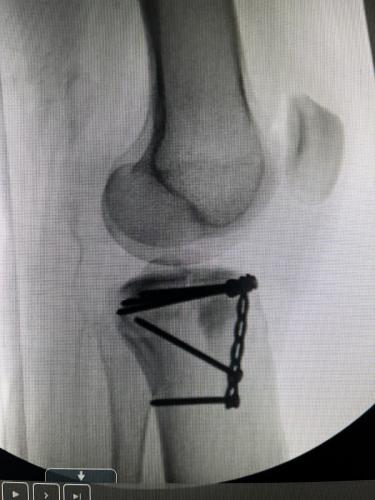

Gallery Fundraising and Volunteering Individual Player Photos Players Banquets & Catapalooza Bumps & Bruises Game Photos Game Day (pre 2020)